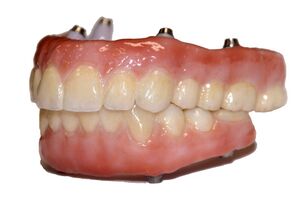

Dental implants

As the rate of tooth loss in the population increases either due to early extraction, trauma, or other systemic diseases, the use of implant therapy has increased as a form of tooth replacement therapy.[29][34] Dental implants are a way to replace missing teeth, as they consist of a titanium surgical component that is placed in the alveolar ridge of the jawbone.[35] The implant then acts as a prosthetic device that can hold either a crown, bridge, or denture on its external surface.[35] For the implant placement to be successful, there needs to be enough alveolar bone to support and stabilize the dental implant.[35] It has been determined that many factors can contribute to the loss of both the vertical and horizontal height of the alveolar bone.[36] These factors can include resorption of the bone after tooth removal (affecting the quality and quantity of the bone), the presence of periodontal disease, the age and gender of the patient, smoking habits, the presence of other systemic diseases, and oral hygiene habits.[37] Although dental implants tend to have a high success rate, of about 99%,[38] studies show that if an implant were to fail, it occurs more often in the front portion of the upper jaw.[39] More research is required to determine why this occurs, but it has been theorized that the alveolar bone in the upper jaw has a thinner cortical plate and lower bone density than that of the lower jaw.[39] As bone loss in the alveolar ridge becomes an increasing problem for the success of dental implants, research has been focused on the development of new surgical techniques and biomaterials that can be used to either maintain current bone levels, or to stimulate the growth of new alveolar bone through osteogenesis.[40][41][42]